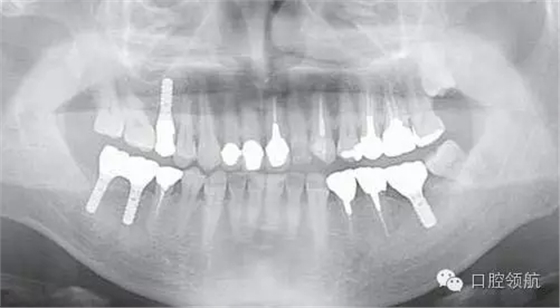

患者,38歲,男性,作為需要全面治療的患者來院?;局委熀螅蚁骂M磨牙區(qū)及右上頜磨牙區(qū),還有拔牙后的左下頜磨牙缺損區(qū),擬進行種植修復。圖1為初診時的曲面斷層影像,問診,模型診斷,曲面斷層檢查均未見異常,因此,最先在右下頜磨牙缺損區(qū),繼而在右上頜磨牙缺損區(qū)植入種植體,這些種植體愈合良好。

圖1 初診時的曲面斷層影像。